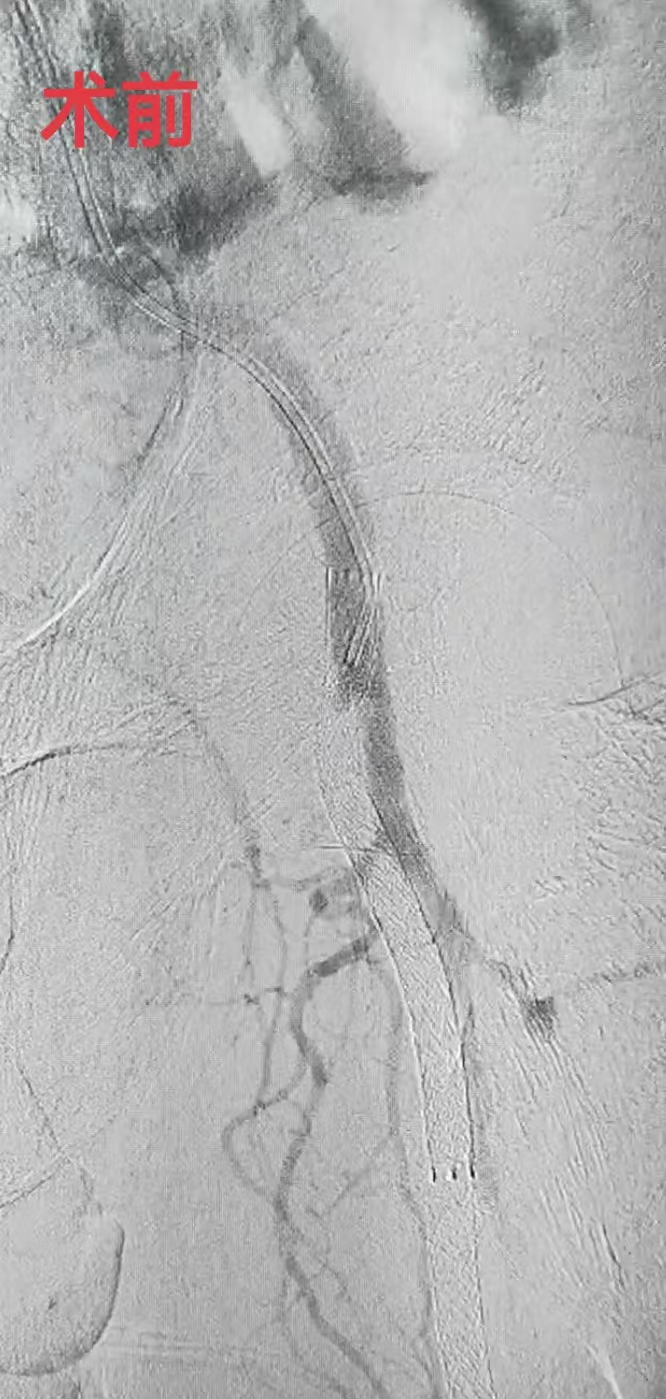

1月9日,中南大学湘雅二医院桂林医院血管外科团队成功为一名82岁的下肢动脉硬化闭塞症患者实施下肢动脉支架内再闭塞疏通手术,术中采用了广西首台装配的Excimer Lacer准分子激光系统,成功开通患者闭塞的股腘动脉支架,为后续治疗创造了有利条件。该手术标志着血管外科在复杂下肢动脉闭塞治疗领域达到了新的技术高度。

据悉,患者曾在外院接受过支架植入手术,此次因左小腿皮肤肌肉溃烂、坏死,慕名来到中南大学湘雅二医院桂林医院治疗,医师诊断其为下肢动脉硬化闭塞症。由于患者左下肢动脉支架已完全闭塞,血管再开通的难度极大,但若不及时治疗,将面临高平面的大截肢风险,严重影响其生活质量。

李鑫主任介绍,TurboElite准分子激光导管是目前国际上最先进的血管减容设备之一,能够通过激光能量精准消融血管内的堵塞物质,尤其适用传统方法难以处理的复杂闭塞病变和支架内再闭塞病变。手术耗时不到两个小时,患者长达30厘米的闭塞支架被重新贯通,辅助药物球囊扩张后,闭塞段血流速度恢复正常。